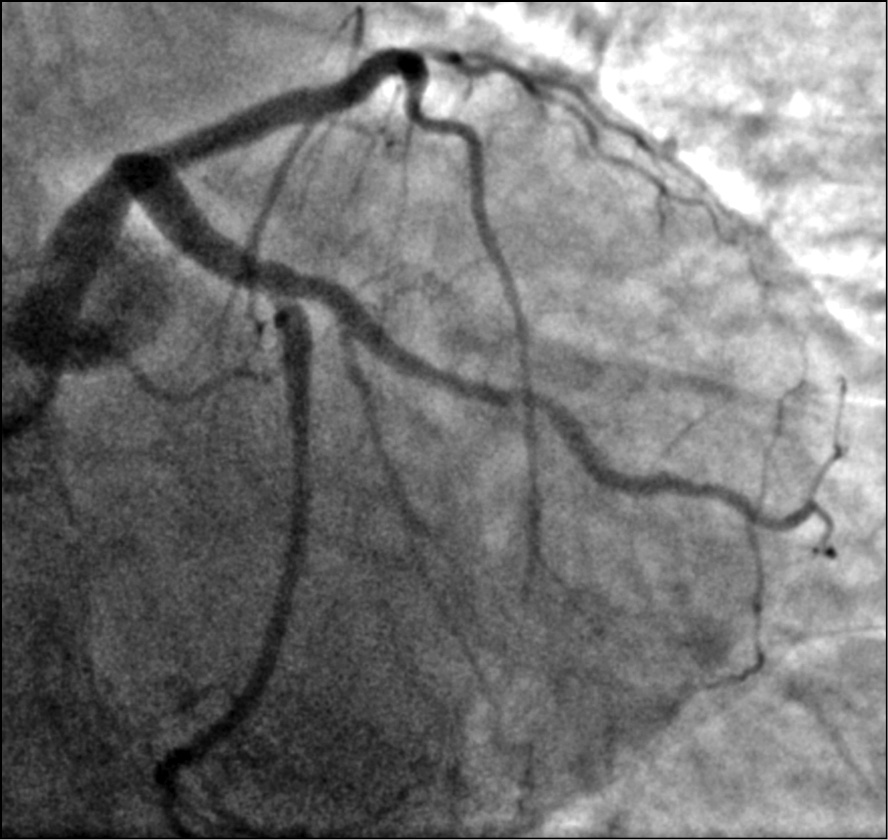

Выполнена коронарография трансрадиальным доступом, на которой выявлено многососудистое поражение коронарного русла: субокклюзия средней трети передней нисходящей артерии (рис. 2), субокклюзия устья первой ветви тупого края (рис. 3), субокклюзия проксимальной части правой коронарной артерии (рис. 4). Диаметр правой коронарной артерии менее 2 мм. Левый тип кровоснабжения миокарда. Тяжесть поражения коронарного русла по шкале Syntax 1 [3] составила 13 баллов (легкая). Рекомендованный метод реваскуляризации миокарда по шкале Syntax 2 [4] — аортокоронарное шунтирование (53,6 балла для чрескожного коронарного вмешательства и 28,6 баллов для аортокоронарного шунтирования).

Выполнено успешное стентирование средней трети передней нисходящей артерии и устья первой ветви тупого края стентами с лекарственным покрытием 3-го поколения «Калипсо» (Ангиолайн, Россия) (рис. 5).

Рис. 5. Пациентка Б., 64 года, с острым коронарным синдромом, находящаяся на программном гемодиализе: контрольная коронарограмма после стентирования передней нисходящей артерии и ветви тупого края